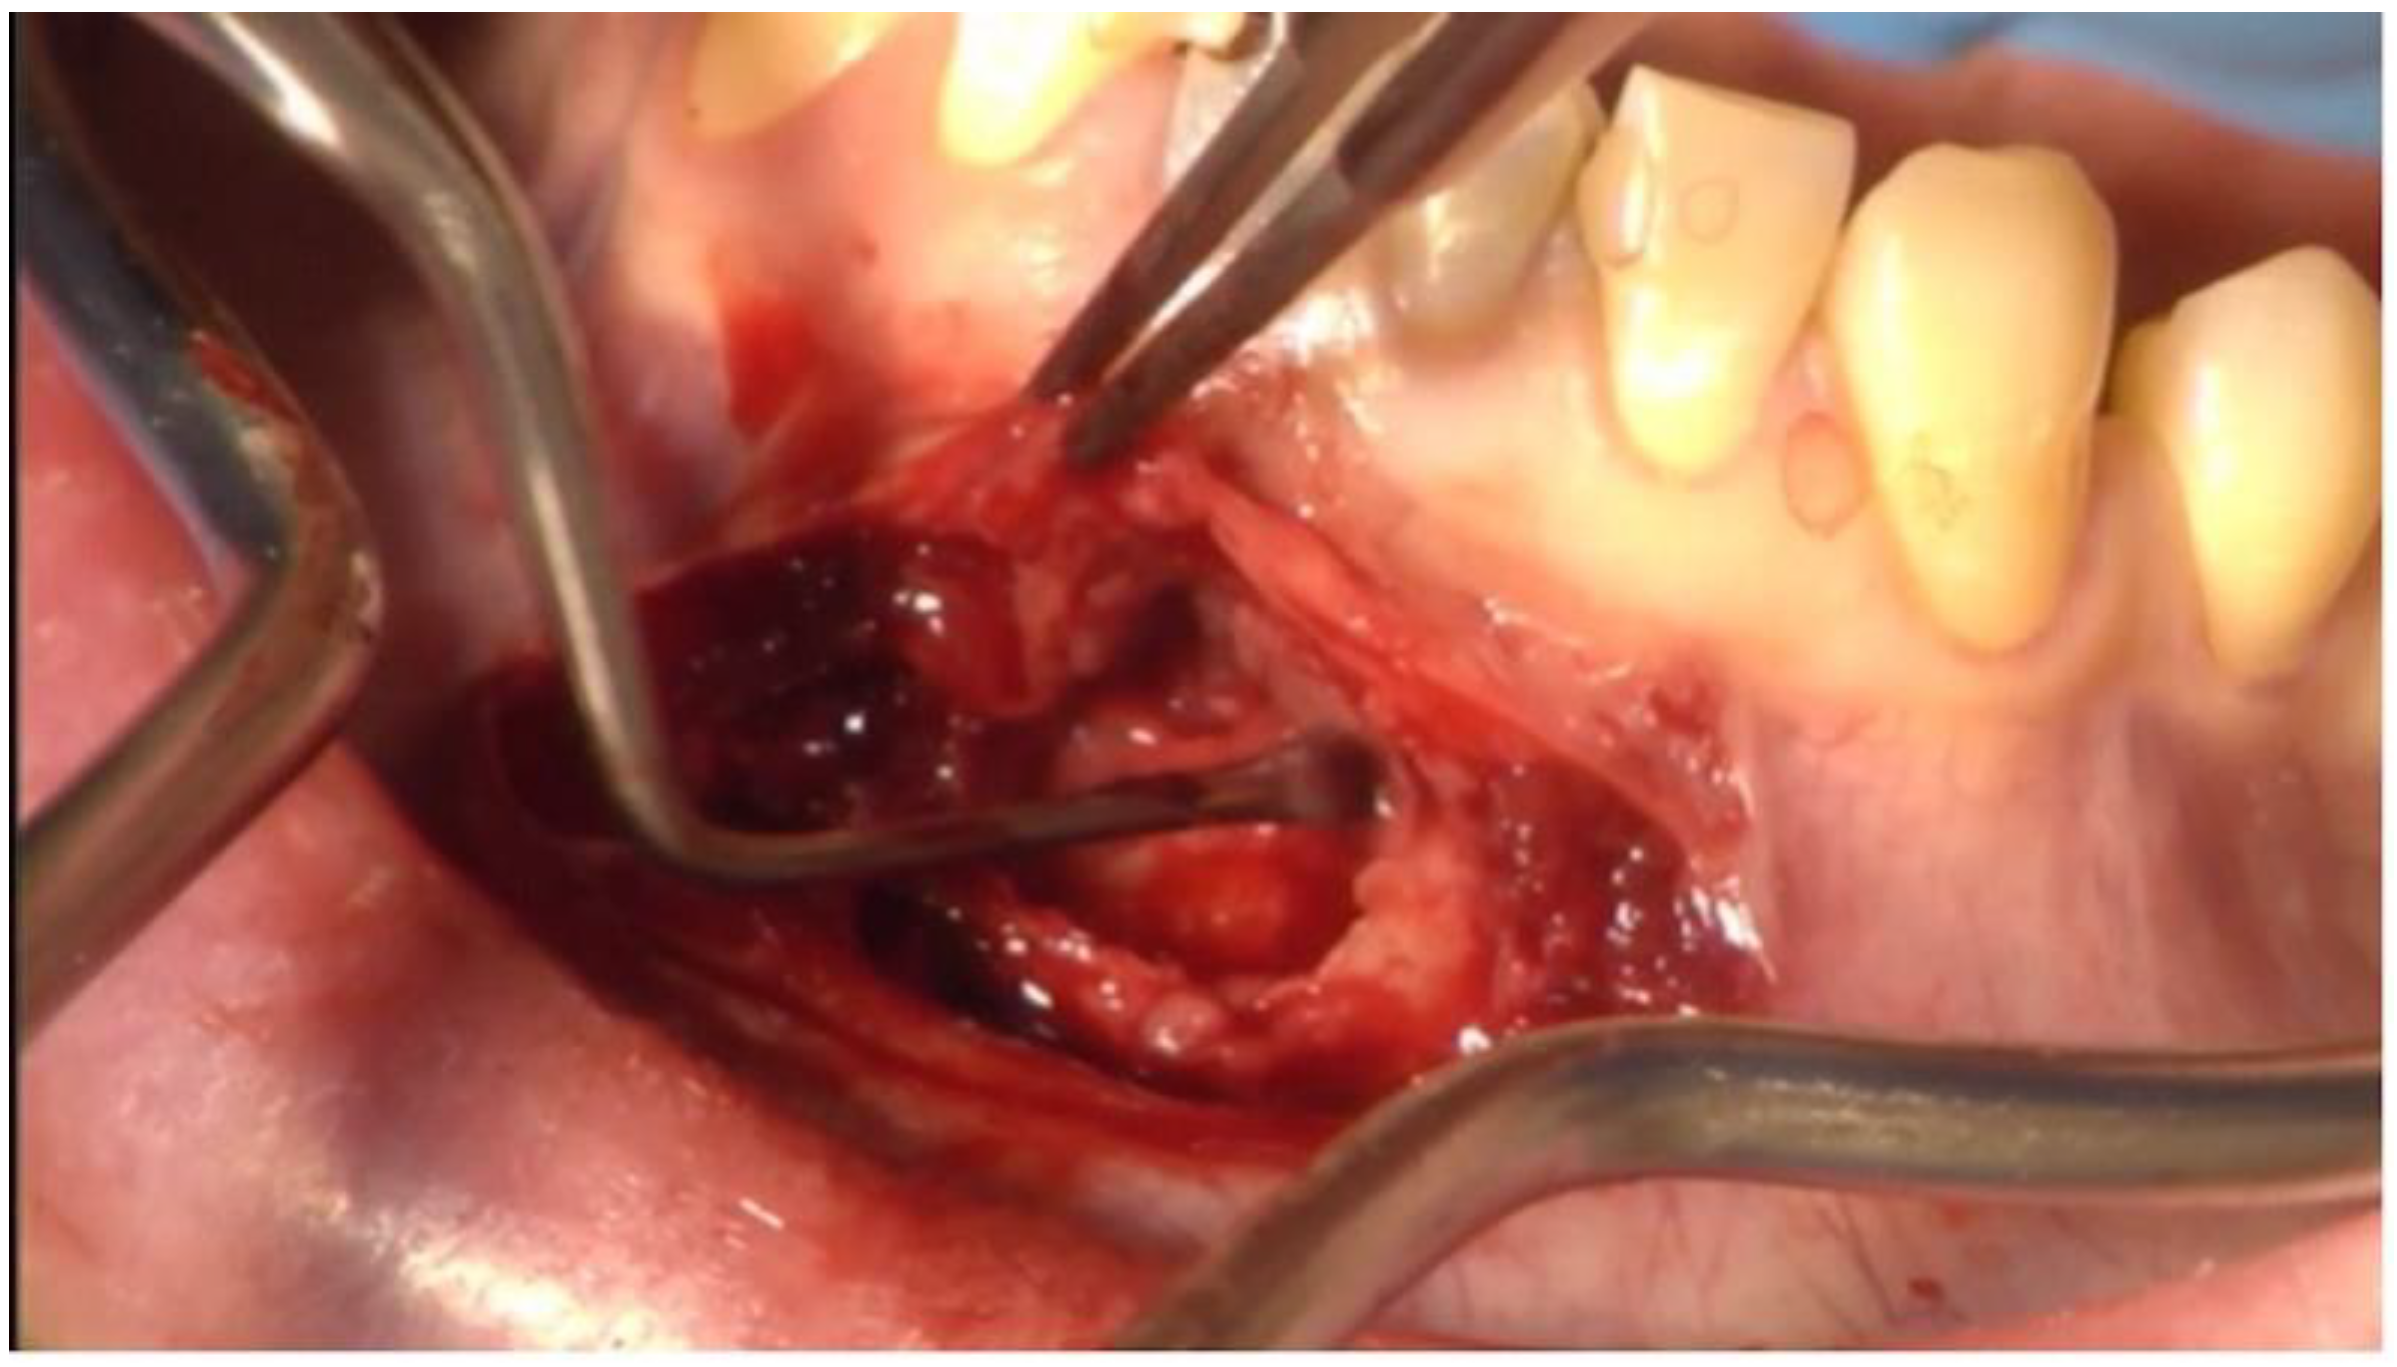

3. Clinical Procedure and Outcome